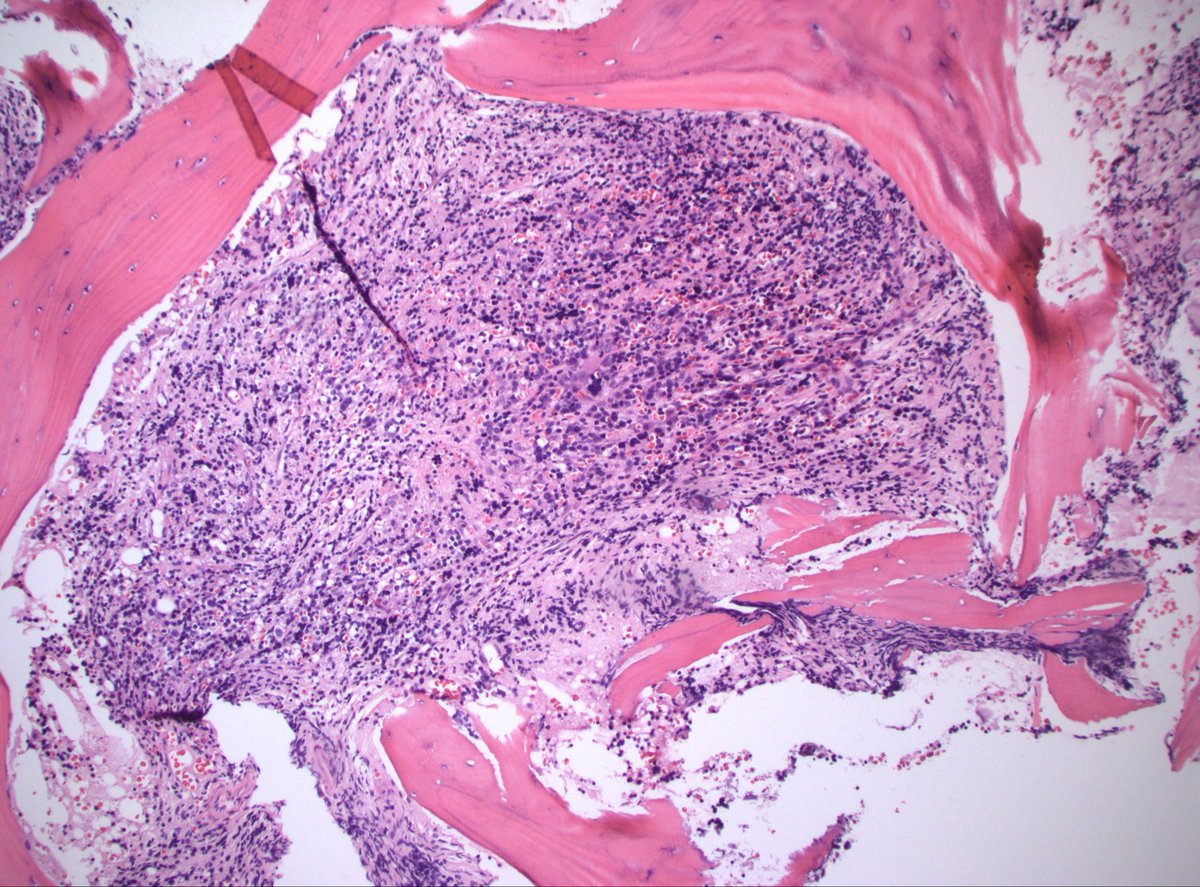

70s M h/o prostate cancer. Multiple bone lesions, this one from iliac. Dx/workup? #PathX #PathTwitter